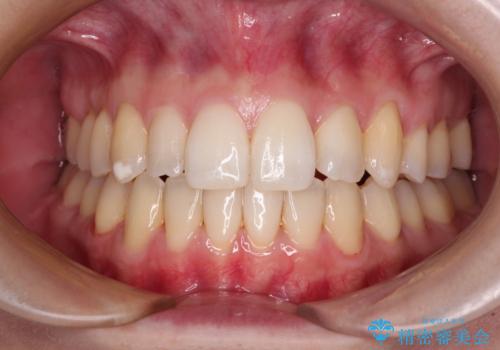

補助装置を用いて奥歯の咬み合わせを事前に改善 インビザラインによる矯正治療

歯列としてはインビザラインでもワイヤー矯正でも対応できるものでしたが、奥歯の咬み合わせを見た時に上顎がやや前方にあり、インビザライン単独では時間のかかってしまう可能性があるため、補助装置を治療当初に使用することで、インビザラインによる治療をスムーズに行えるように計画しました。

インビザラインは得意・不得意の差がはっきりとしているため、補助装置やワイヤー装置などをうまく活用することで、治療期間を短縮するとともに、より理想的な仕上がりを達成することができます。